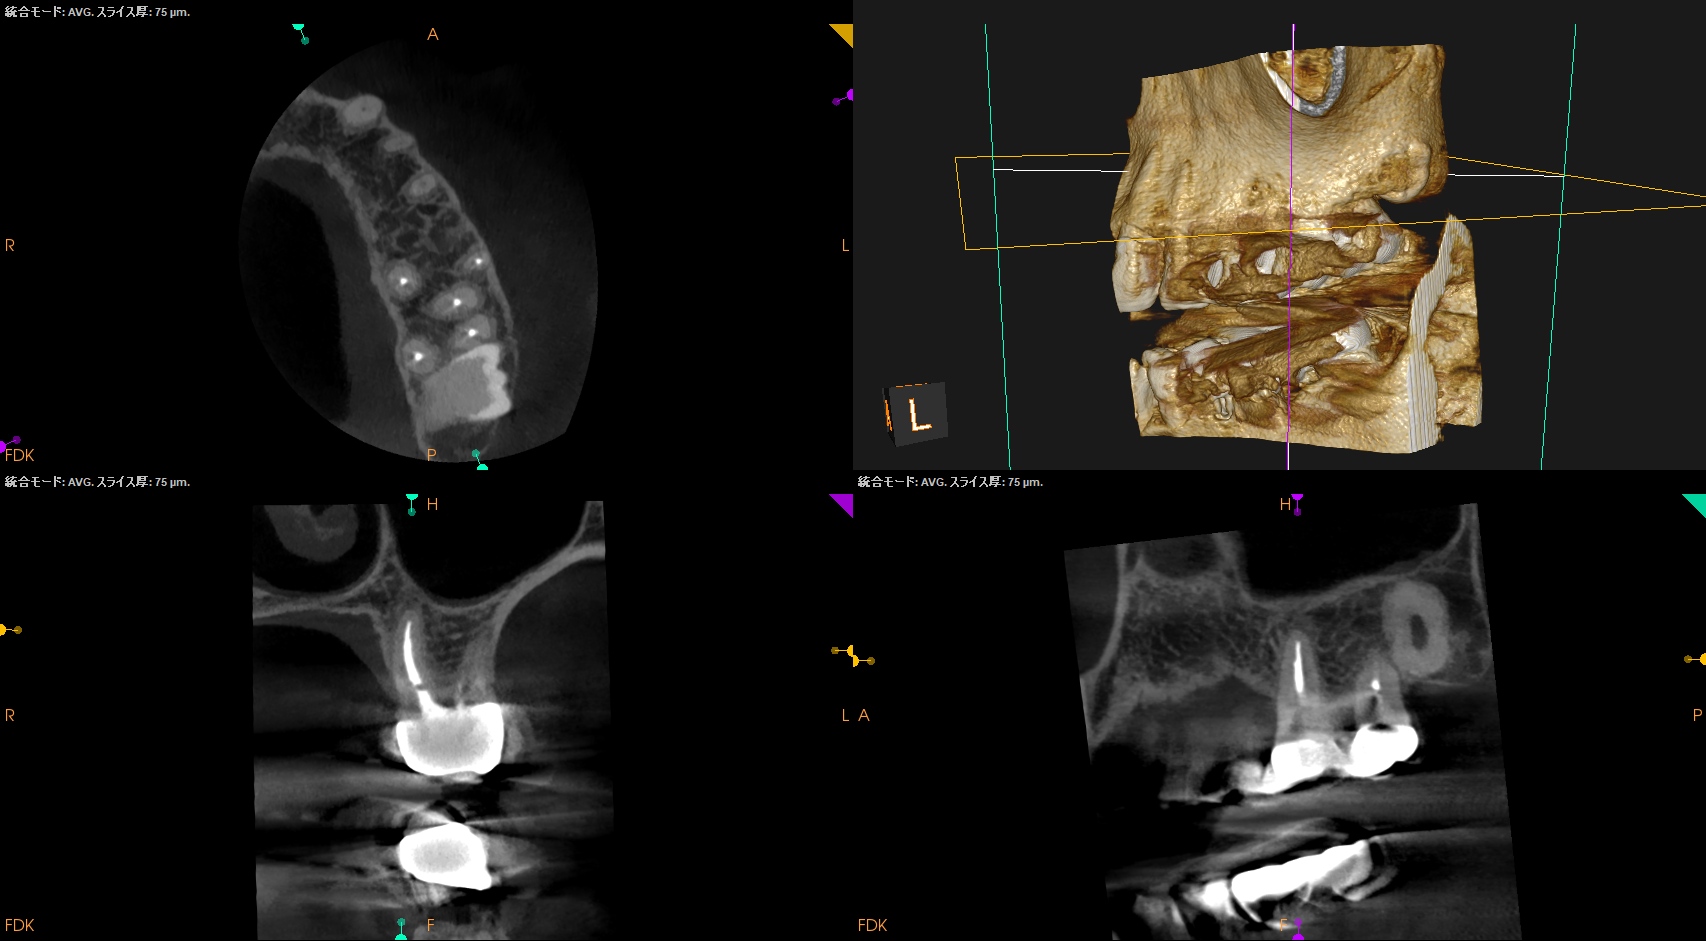

#14 Post-op 1yr recall(2026.3.27)

PA, CBCTを撮影した。

MB

DB

P

外科時と比較した。

問題は劇的に解消した。

ということでこの日で終診とさせていただいた。